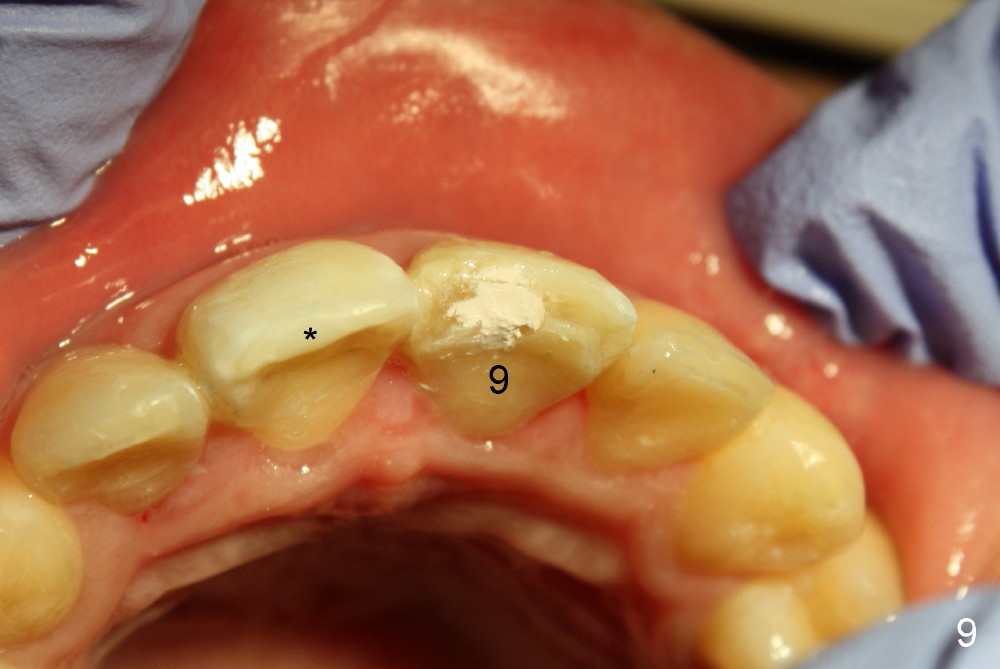

The patient returned to finish RCT 1.5 months later (Fig.6). Gutta percha was removed as much (high) as possible (Fig.7 >). In order to prevent butterfly rubber dam clamp interference in access and GP removal, smaller clamps should be placed in the neighboring teeth (Fig.8). When RCT was done, the tooth #9 was still the darkest (Fig.9). Thermoplastic tab was used to make local external bleaching tray (Fig.10 *). The patient and his mother were instructed to do external and internal bleaching daily.